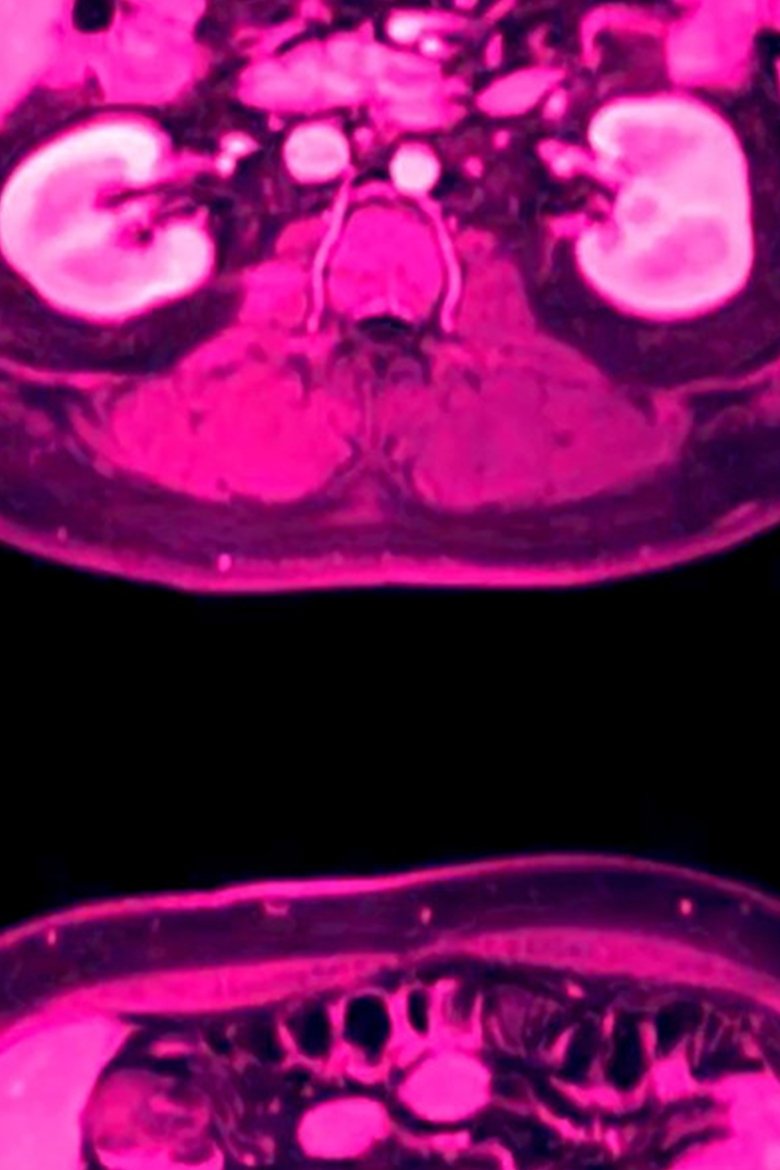

"in ocula oculorum" interrogates the unknown and the internal, in both subject matter and experience. Dealing with the contemporary state of perpetual doom, the film contemplates various stages of life and death from the point of view of our human bodies and perceptual systems. It explores beta movement and phi phenomenon, pushing the limits of intermittence and persistence of vision, playing with our innate desire for continuity and cohesion by forcing image slip.